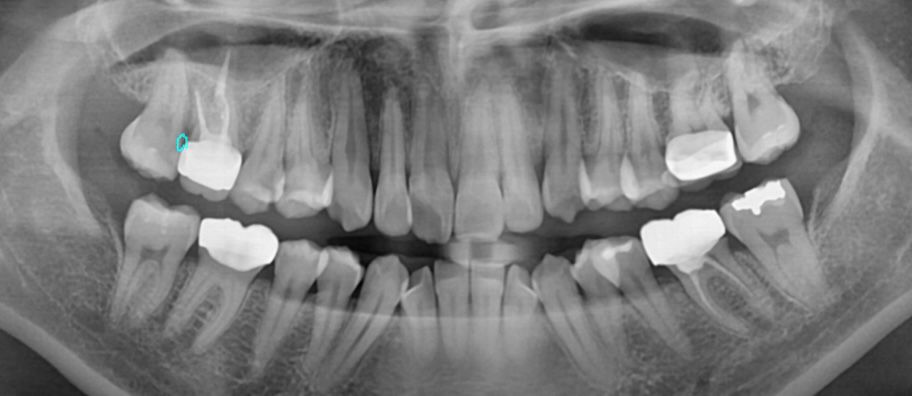

안녕하세요 평소 불편함이 있다고 생각을 못했는데 스케일링 받으러 갔다가 한 치아에 충치가 크다고 옆에 붙어있는 치아까지 두 치아 전부 인레이를 하던, 신경치료 후 크라운을 하자고 합니다. 외관상 제가 사진을 보니 한 치아는 충치가 심해서 구멍이 났어요. 근데 옆치아까지 신경치료 후 크라운을 하자고 하시고 제가 치과치료가 너무 무섭다고 하니 인레이로 최대한 해보자고 했습니다. 오늘 충치치료하고 인레이만 결제했는데 충치치료 끝물쯤 신경과 가까워서 아플 수 있다고 하셨고 실제로 아프고 시렸어요 마취를 했는데도. 제가 멀쩡한 치아도 마취하고 신경에 가깝게 치아를 깎으면 아플 수 있냐 하니 간호사 두 분이 대답이 다르고 의사분은 바빠보여 묻지를 못했어요. 일주일정도 시리고 불편하면 바로 크라운 하자고 하네요. 이 치아 둘 다 애초에 떼우는 걸로는 안됐던 치아였는지 궁금해서 질문드립니다. 검정 부분이면 썩은거라는데 비전문가인 저는 검정부분이 이빨 전체에 다 보여서 과잉진료인지 봐주세요..

• 1번 째 사진

• 사진으로만 봤을 경우에는 충치가 인접면에 매우 크게 있는 것으로 보입니다. 충치를 제거했을 때 신경이 노출이 된다면 신경 치료에 크라운 치료를 하는 것이 좋습니다. 인레이치료를 한다고 해도 범위가 넓기 때문에 보철물이 잘 탈락하거나 깨질 가능성이 높습니다. 자세한 확인을 위해서 치과에서 진료를 받아보는 것을 권해드립니다

엑스레이 상으로 보면 충치가 상당히 진행된 상태 같습니다. 저정도면 신경치료를 해야될 가능성이 높아 보이긴 합니다.

치아를 간단하게 치료하기에는 충치의 범위가 매우 큰 편이며 신경치료까지 하더라도 전혀 과잉이 아닙니다.

아래 그림에서 동그라미친 부분이 충치입니다. 충치가 신경(가운데 검은색 줄)과 근접해 있었기 때문에 충치 제거과정에서 신경이 간접노출 또는 완전노출되었다면 시리고 아팠을 수 있습니다. 이런 경우 신경치료는 불가피합니다. 다음 내원전까지 증상을 잘 살펴봐야 합니다.